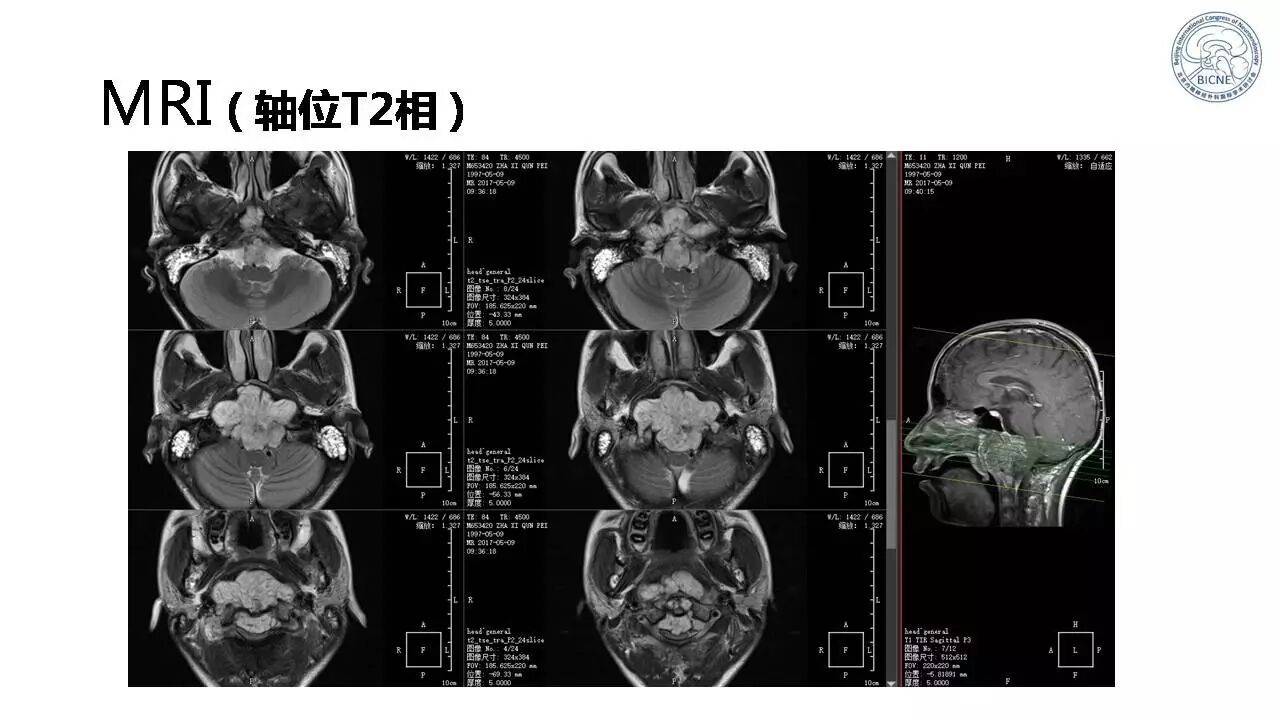

(一)张亚卓教授:脊索瘤经鼻内镜下治疗

![]()